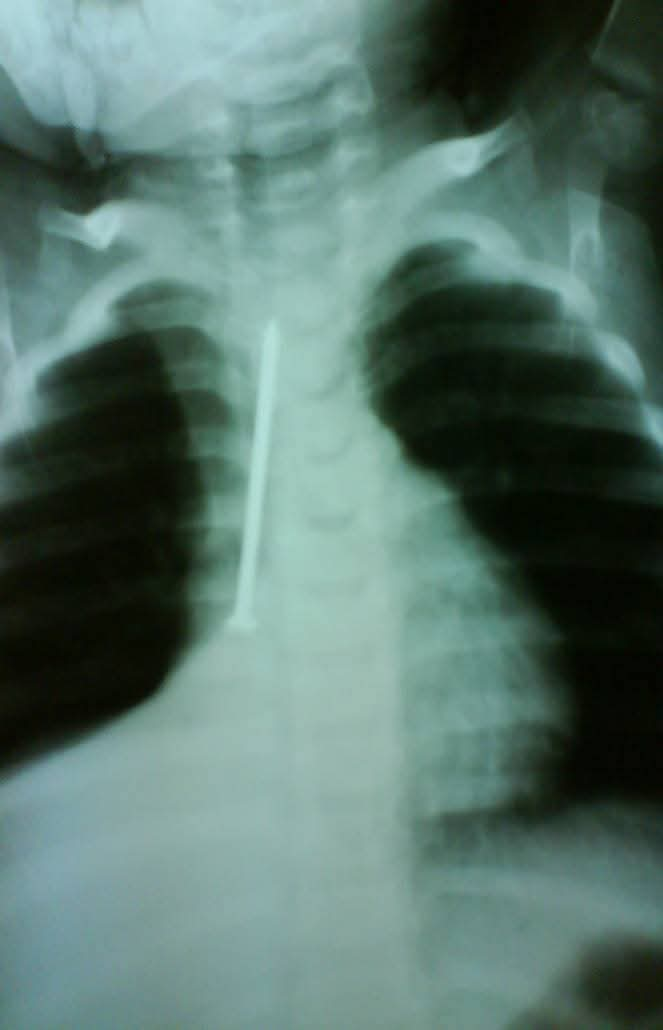

وأضاف قائلًا: "كانت الطفلة في حالة طبيعية تمامًا، تتنفس بشكل جيد ولا تعاني من أي صعوبة في البلع، لكن أمام إصرار الأم على أنها بحثت جيدًا في المنزل، قررت إجراء أشعة على صدر الطفلة، لتظهر المفاجأة الصادمة: مسمار طويل يمتد بطول القفص الصدري تقريبًا."

وأشار إلى أنه تم إدخال الطفلة إلى غرفة العمليات على الفور، وتمكن الفريق الطبي من استخراج المسمار بنجاح، دون حدوث أي إصابة أو مضاعفات.